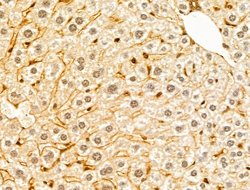

Invitrogen™ GABPB1 Polyclonal Antibody

Antibody detects endogenous levels of total GABPB1.

| Immunohistochemistry (Paraffin), Western Blot, Immunocytochemistry | |

| A synthesized peptide derived from human GABPB1(Accession Q06547), corresponding to amino acid residues V264-D314. | |

| Human, Mouse, Rat | |